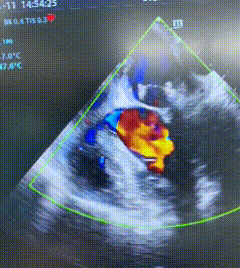

术后超声显示,王先生二尖瓣反流完全消失,瓣膜启闭功能恢复正常。